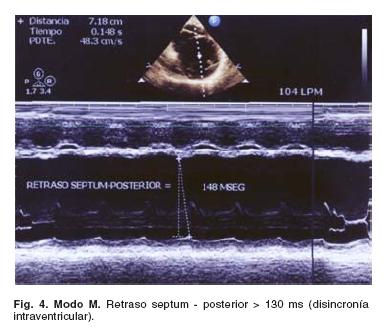

Disincronía intraventricular

Un período pre-expulsivo aórtico (> 140 mseg) medido desde el inicio de la onda "q" del ECG hasta el inicio del flujo aórtico es considerado como disincronía intraventricular (Fig. 3). El período expulsivo, medido como el intervalo de tiempo entre la apertura valvular aórtica y el cierre, puede estar reducido debido al retraso del inicio de la contracción ventricular así como del tiempo de contracción y relajación ventricular. De la misma manera se puede obtener a través del modo M de la cavidad ventricular izquierda, a nivel de los músculos papilares el retraso de la activación septal en relación con la pared posterior; un retraso mayor de 130 mseg se considera como disincronía intraventricular. Este último método tiene como inconveniente la cardiopatía isquémica y a los cambios de presión y/o volumen del ventrículo derecho10 (Fig. 4).